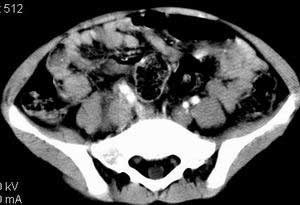

| 患者,男,9岁,因右下腹包块入院,血象不高,不规则发热,常超40度。 平扫: ![]() ![]() ![]() ![]() ![]() ![]() ![]() ![]() ![]() ![]() ![]() ![]() ![]() ![]() ![]() ![]() ![]() ![]() 增强: ![]() ![]() ![]() ![]() ![]() ![]() ![]() ![]() ![]() ![]() ![]() ![]() ![]() ![]() jiajie发言:骶椎右前区不规则软组织肿块,边缘光整,密度均匀,增强后均匀强化,右腹股沟区可见肿大淋巴结,临床有时发热,考虑淋巴瘤,儿童盆腔肿瘤应与神经母细胞瘤和横纹肌肉瘤鉴别。 longzhanghui发言:印象:盆腔右后壁不规则软组织肿块,并向前延伸.似为多个肿块融合,呈中等强化.初步考虑淋巴瘤. 听蝉观竹发言:右侧髂内、外组淋巴结肿大,从其形态和融合的情况看,同意大家意见-----考虑恶性病变,但是9岁男孩还要注意检查睾丸情况,有无隐睾? 常常类似情况是隐睾发生精原细胞瘤淋巴结转移,这个病例也要注意这一点!!! 广东凌发言:大家好,在这里我想说一下个人观点,我建议上传图片的同志能否辛苦一点就是把病史和图片都上传完整一点,比如这个病人的腹膜窗,并且这个病人的肠道的准备也是不怎么好,就从现有的质料看:病灶属于淋巴结肿大当无大的争议,有融合趋势,其内无坏死,边缘强化为主,故考虑:淋巴瘤!建议用腹膜窗看一下和肠道的关系! 阿圣发言:病灶属于淋巴结肿大当无大的争议,有融合趋势,其内无坏死,边缘强化为主,故考虑:淋巴瘤 结果是:淋巴瘤 病例来源:ct762。由宁静致远发布: http://www.radinet.com.cn/forum_view.asp?forum_id=4&view_id=2182 |